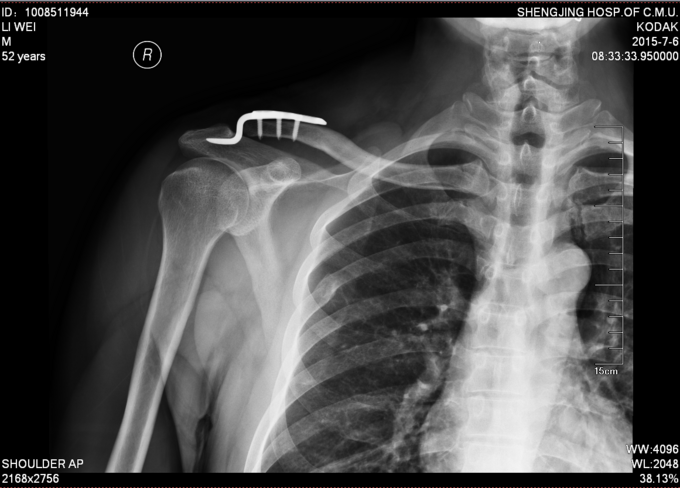

诊断:右肩锁关节脱位 入院后完善检查,完善心电图,生化检查后。局部消肿后,查无手术禁忌症后行右肩关节脱位锁骨钩钢板内固定术